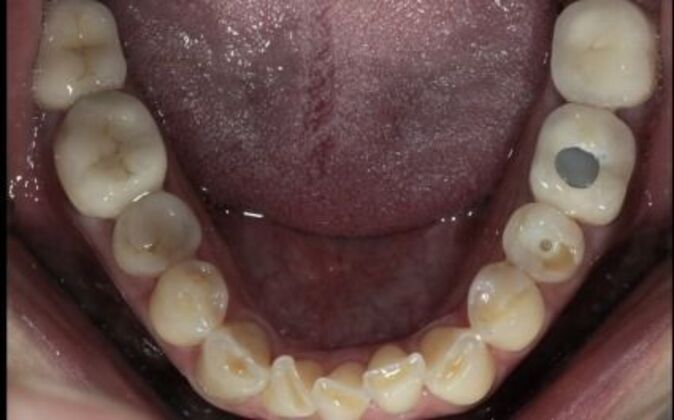

Full Mouth Reconstruction: Risa

Full mouth reconstruction. When you see a client at a young age with so much dental work to begin with you consider your options carefully. You need to be aggressive in approach and conservative in maintaining as much of the healthy tooth structure. Have to consider the age of a patient whenever you embark on a major dental work especially when it involves redoing everything, repositioning and re-establishing a brand new bite position and correcting the inflammatory gum response from previous dental work. You cannot approach a case like this with a limited treatment plan that only addresses a few teeth. If this case is treated one tooth at a time you may leave the patient a “dental cripple”. By that I mean that this patient will constantly be at dental offices for the rest of her life addressing one broken down tooth after another until a cascading domino effect will render all the teeth in a hopeless condition. Here is a situation where we are dealing with multiple problems 1-bite collapse and malfunction 2-gum disease exacerbated by poorly fitting crowns 3-decaying teeth affecting the health of the roots This case had to consider all of these issues. Must understand that this patient is very young and has many years ahead of her so the dentistry has to be done meticulously, conservatively,aggressively and expeditiously. It’s a tough balancing act but as dentists we need to be realistic about our treatment objectives and have a proper plan that addresses dental breakdown. We were able to achieve the esthetic and functional concerns of the patient. Although we felt the color of the teeth were too bright. We do need to consider patients desires since they need to live with this for the rest of their lives and ultimately they need to be happy